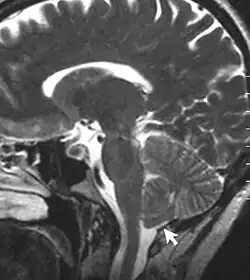

Chronic secondary headache or orofacial pain is a result of an underlying disorder.[24] Chronic secondary headache or orofacial pain can be caused by ischemic stroke, nontraumatic intracranial hemorrhage, arteritis, unruptured vascular malformation, pituitary apoplexy, genetic vasculopathy, increased cerebrospinal fluid pressure, Chiari malformation type I, intracranial neoplasms, epileptic seizure, substance withdrawal,[24] bacterial meningitis, meningoencephalitis, viral meningitis or encephalitis, brain abscess, intracranial fungal or other parasitic infections, hypoxia, hypercapnia, dialysis, arterial hypertension, and hypothyroidism.[25]

- Chronic headache or orofacial pain associated with non-vascular intracranial disorder